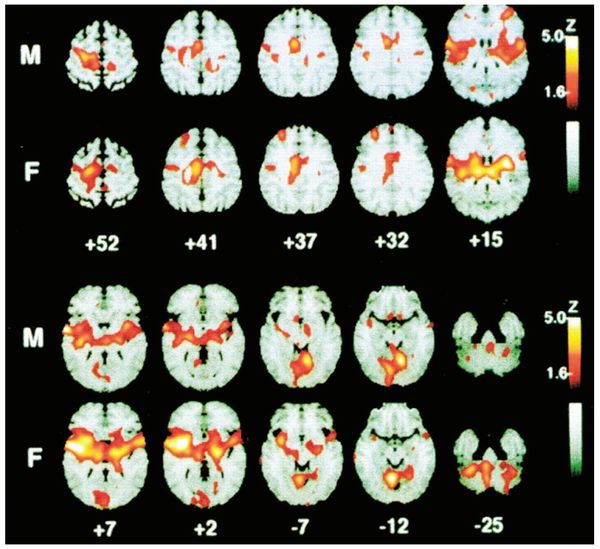

張博士以一個經典的研究[4]講解,研究主要圍繞長期痛楚對人造成的各種影響以及如何提供醫療照顧。研究報告中引述早在1991年已有學者透過PET scan (Positron emission tomography) 觀察腦部數個區域,包括體覺皮質區(primary and secondary somatosensory cortex), 前腦島(anterior insula), and (前扣帶皮層 (anterior cingulated cortex, ACC),從而推斷兩性對痛楚的敏感度及忍耐程度的分別。透過腦部的一些掃描圖片,發現人體在遇到50度高溫的刺激時,兩性腦部會透過不同的區域作出反應,而反應的程度亦有所不同(圖7)。

圖7 A positron emission tomography scan image of rCBF responses of 10 males (M) and 10 females (F) to repetitive noxious heat stimulation (50°C) of the left volar forearm. Significant activation of the contralateral anterior cingulate cortex, premotor, insular cortex, ipsilateral insula, and bilateral cerebellar vermis has been identified. From “Gender Differences in Pain Perception and Patterns of Cerebral Activation During Noxious Heat Stimulation in Humans,” by P. E. Paulson, S. Minoshima, T. J. Morrow, and K. L. Casey, Pain, 76, 1998, p. 227. Copyright 1998 by the International Association for the Study of Pain. Reprinted with permission.

研究顯示女性對於感受痛楚時腦部十分活躍,而有反應的區域比男性多,因此較男性更易感到痛楚;但有趣的是,即使女性如此容易感受痛楚,但卻比男性更能忍受痛楚。張博士提到可能與女性考慮痛楚的意義有關,例如生產,女性生產時的痛楚很巨大,但在生育時會「死忍」,並且很快便會被新生命的喜悅掩蓋痛楚,因為生育對女性的意義令她足以忍受。